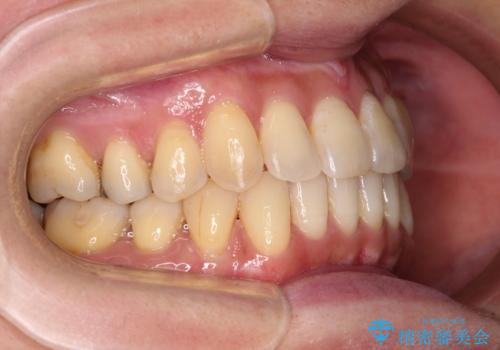

- 前歯のクロスバイトが気になり、インビザラインによる矯正治療を希望して来院された患者様です。

上顎側切歯(上の真ん中から2番目の歯)が舌側転位している場合、インビザラインでは仕上げきれないことが多く、更には無理して動かそうとすると歯髄壊死を起こすリスクが高いと言われています。

インビザラインで歯列を移動する前に、上顎前歯をワイヤー矯正で整え、その後上下歯列をインビザラインにて矯正治療を行うこととしました。

舌側転位している側切歯特有の、切縁の位置が不揃いであったり、根元が内側に引っ込んだ状態であったりという、インビザライン独特の仕上がりになることなく、きれいに整った歯列とすることができました。